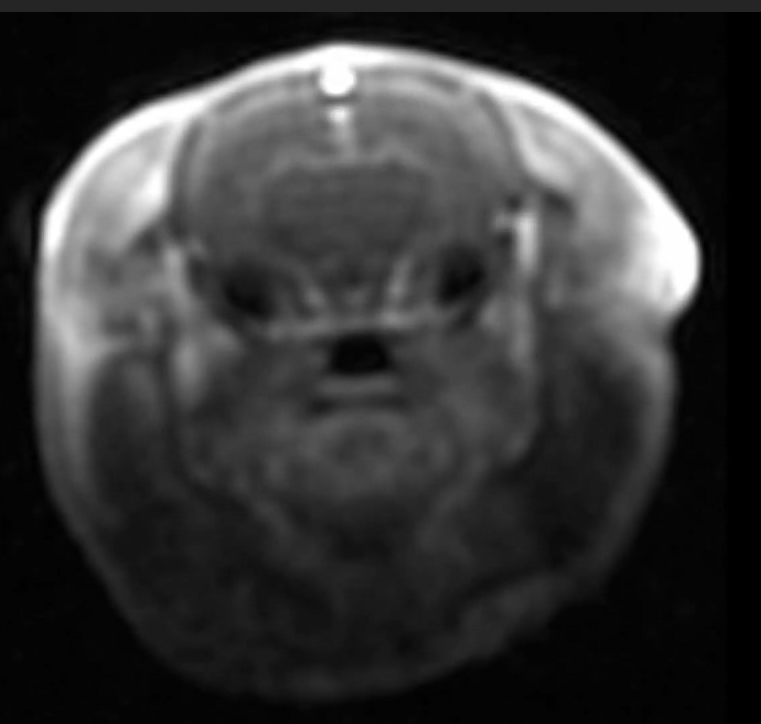

Examples of images acquired by our 7T MRI

MRI images of rat spine, brain tumor, fat imaging and mouse in-utero